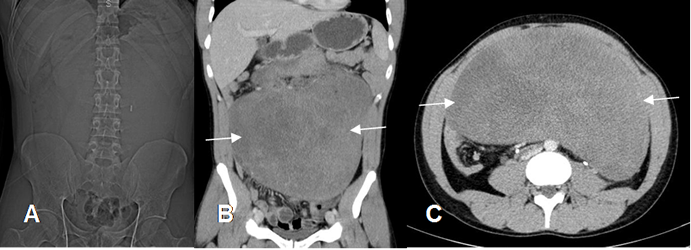

Fig 118.Tumor desmoide.

A: Rx AP. Efecto de masa periumbilical, que desplaza las asas intestinales.

B: TAC reconstrucción coronal y C: TAC axial. Gran lesión de consistencia sólida y heterogénea, que produce efecto de masa sobre los órganos abdominales, por tumor desmoide.